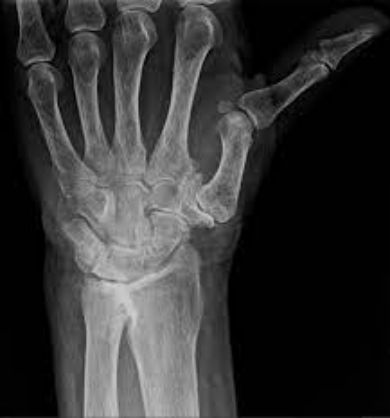

Les radiographies de face et de profil du pouce et les incidences de Kapandji confirment le diagnostic clinique et permettent d'apprécier l'importance de la destruction articulaire. On recherche également une atteinte arthrosique des autres articulations de la main.

Radiographie de rhizarthrose — arthrose du pouce

Le diagnostic est clinique : la douleur à la base du pouce et la perte de force lors de la pince orientent immédiatement, et la radiographie confirme l'arthrose. Les radiographies de face et de profil du pouce, complétées par les incidences spécifiques de Kapandji, permettent d'apprécier l'importance de la destruction articulaire et la subluxation associée. Le bilan radiologique recherche également une atteinte arthrosique des autres articulations de la main, qui est fréquente. Aucun autre examen complémentaire n'est nécessaire au diagnostic.